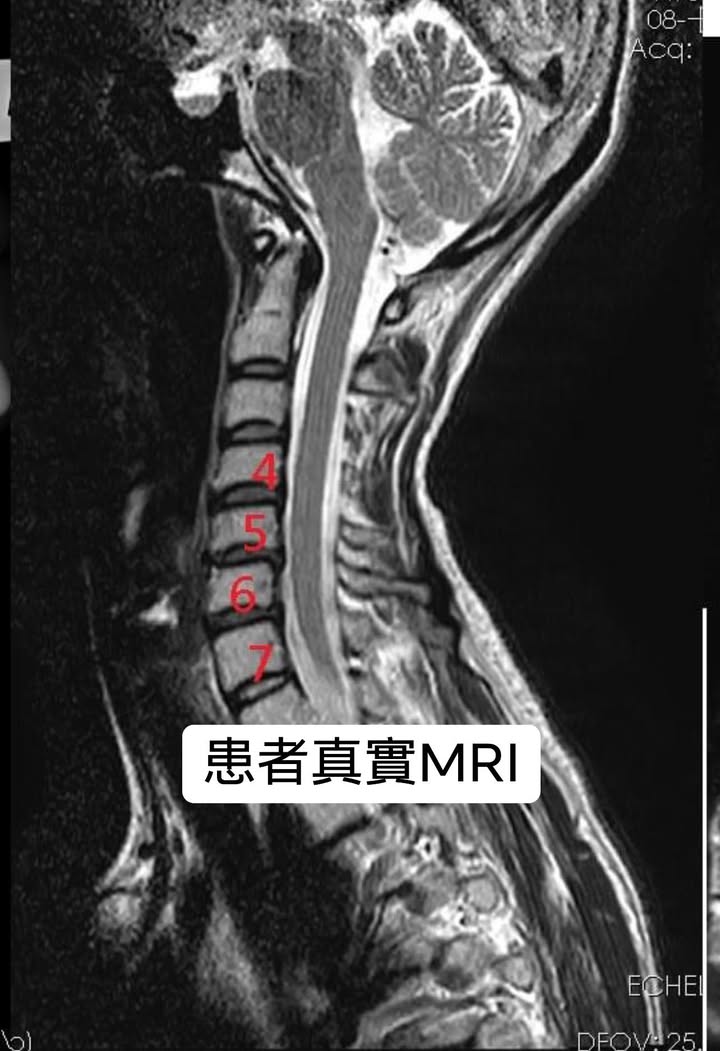

醫案:李小姐抱怨6個月前開始不明原因疼痛,之後合併自律神經失調嚴重症狀,食慾下降很誇張,幾乎肚子都不餓,在很短的時間體重暴瘦快十公斤,在當地診所自費打過1次PRP自體血小板生長因子,疼痛情況是整天不定時抽痛!雙耳持續高頻耳鳴很困擾,只要身體變換一下姿勢就會誘發胸悶跟心悸!嚴重時還有恐慌,不敢去人多的地方,例如公車站跟地鐵,我們請患者填寫頸椎自我量測表,結果赫然發現有好幾個選項都被勾選到了⋯⋯⋯⋯

長期保守治療無效者,且經 CT 或MRI檢查明確診斷,或出現大小便失禁,跟肌肉萎縮患者應接受手術治療。